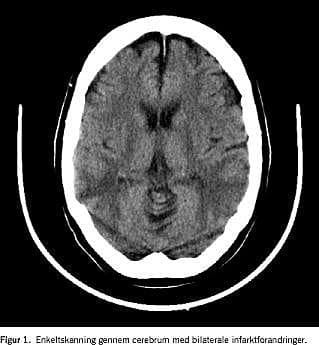

I det fjerde døgn ændredes patienten cerebralt, og der opstod krampeanfald, som blev behandlet med diazepam og valproat. En computertomografi (CT) af cerebrum viste bilaterale symmetriske iskæmiske områder på overgangen mellem a. cerebri media og a. cerebri posteriors forsyningsgebet, hvilket blev fortolket som hypoksisk encefalopati (Figur 1). En elektroencefalografi (EEG) viste svært abnorme forhold. En transkranial Doppler-sonografi var uden tegn på abnormt flowmønster og gav ikke mistanke om rebound vasospasmer eller cirkulationsstop i de større intracerebrale kar.